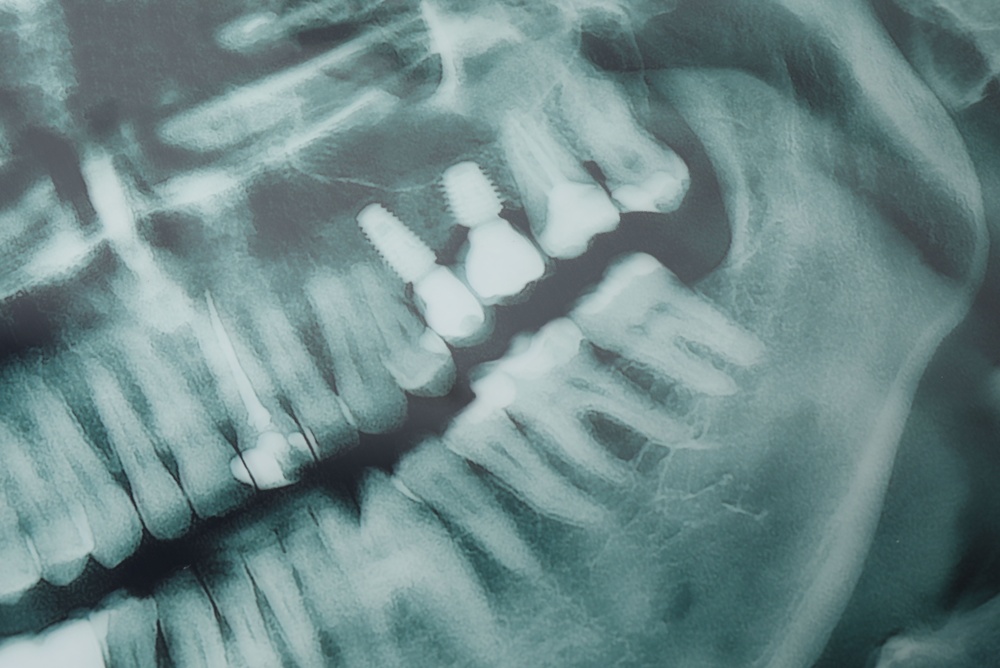

An implant is made of three main parts: the implant (the post that goes into bone), the abutment (a connector), and the crown (the visible tooth). Unlike dentures that sit on gums or bridges that use neighboring teeth for support, implants replace the root. This helps keep jawbone strong and gives more stability than removable options.

A consult includes an exam, medical review, and imaging. Cone beam CT (CBCT) scans map bone, nerve paths, and sinus locations for precise planning. Good planning reduces surprises and speeds treatment.

If a tooth needs removal, that may occur first. The implant is placed into the jaw and left to heal and fuse with bone (osseointegration), which can take weeks to months. After healing, an abutment is attached and a custom crown is placed. Practices with an in-house lab can make restorations faster and fit more accurately.